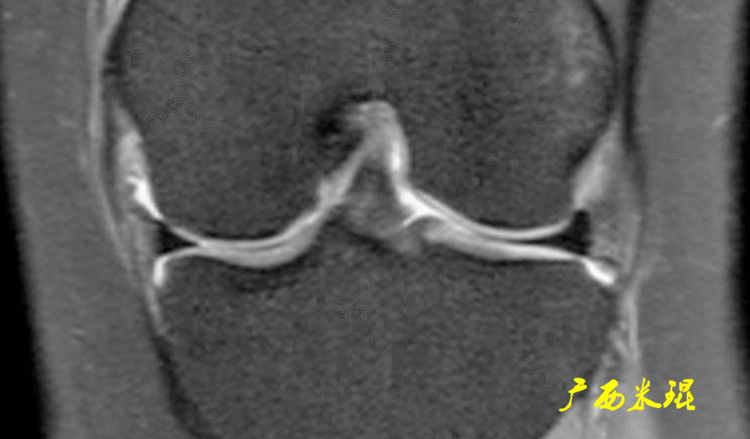

(1)假桶柄MR冠状位上偏后的层面,“C”形或“O”形的内外侧半月板偏后侧层面有可能同时扫描到半月板体部和后角,容易误诊为桶柄状撕裂,而矢状位或横断位上半月板形态是正常的。

下面这张MR冠状位显示为内侧半月板后角的假桶柄,其母体(图片中内侧的那一部分半月板)并没有变小、形态及信号均正常。

下面这张MR冠状位显示为外侧半月板后角的假桶柄,尽管在髁间窝发现半月板信号,但其母体(图片中外侧的那一部分半月板)并没有变小、形态及信号均正常。